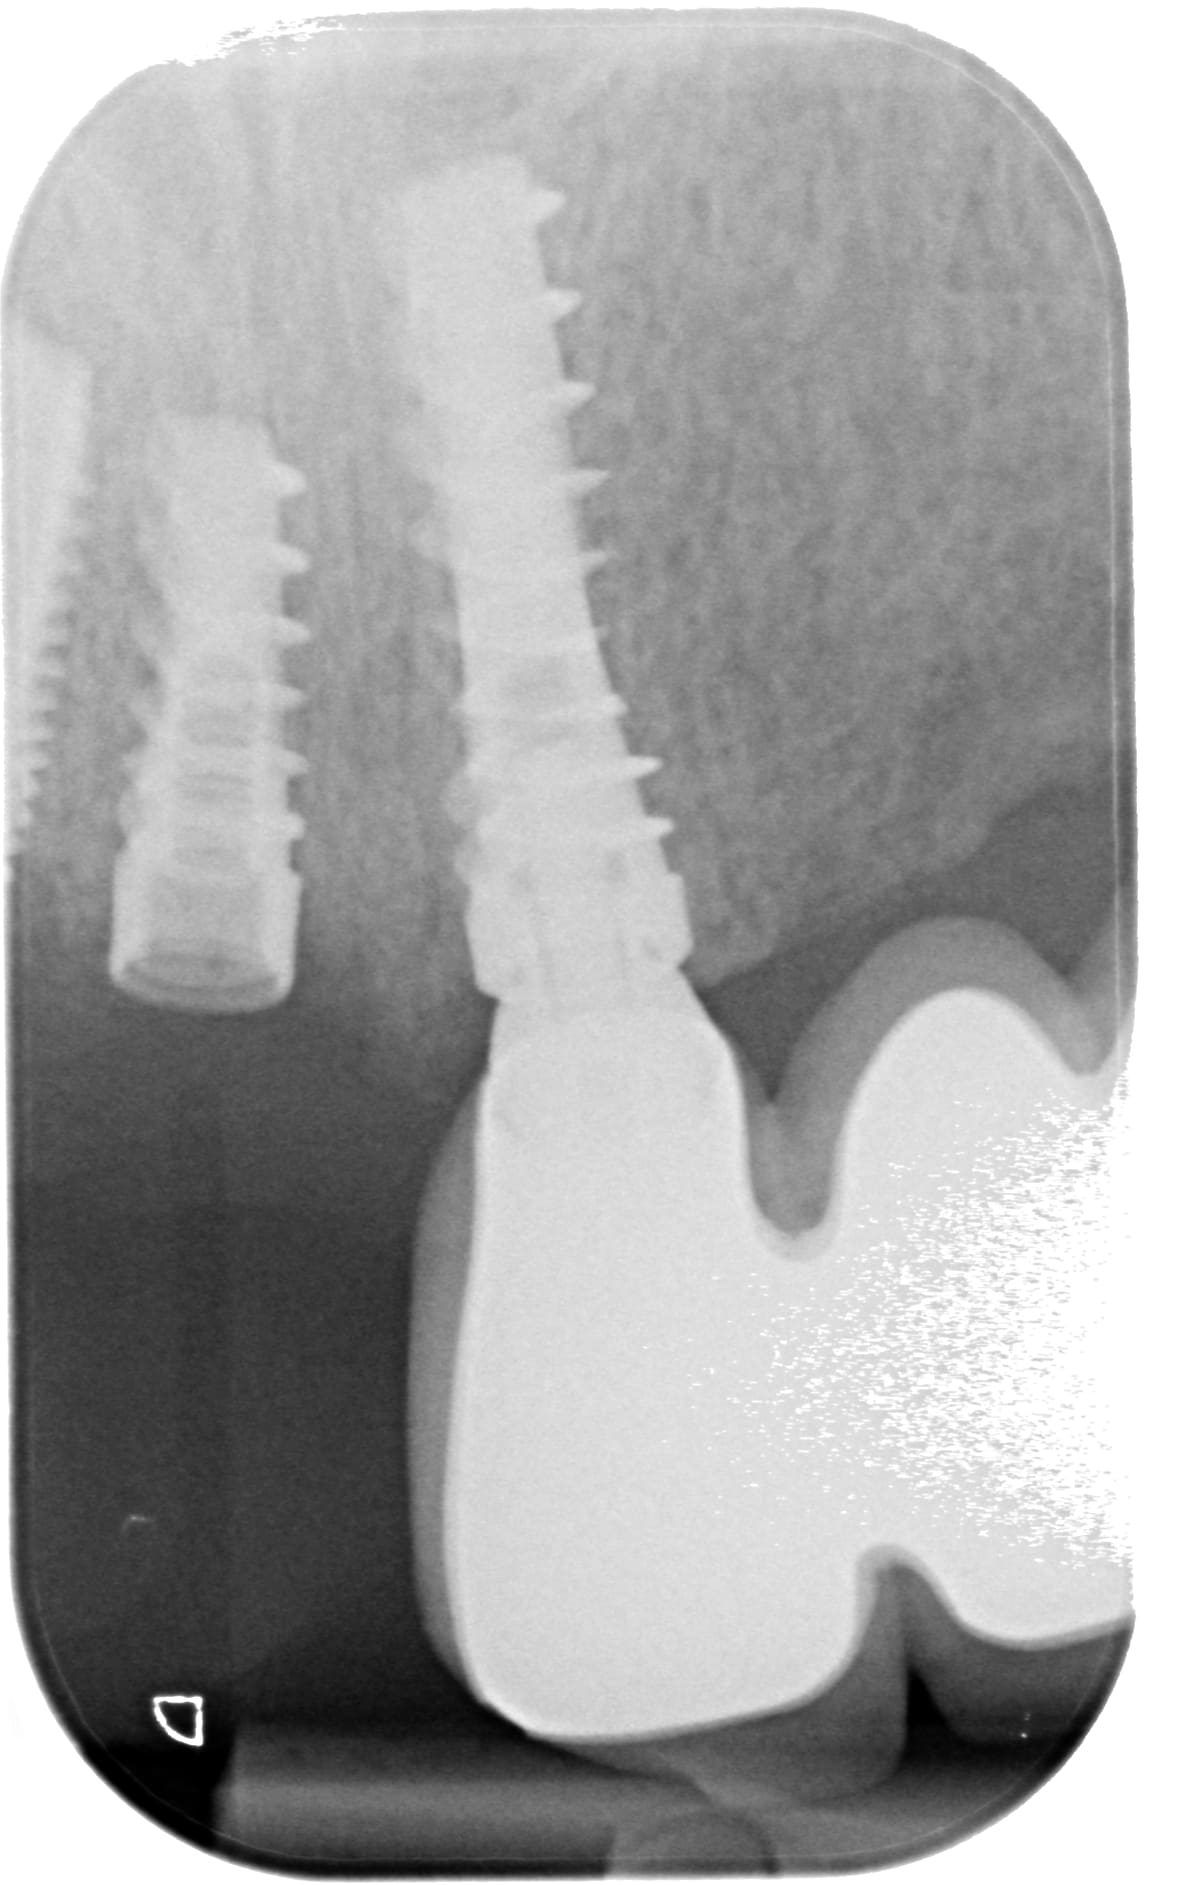

bonjour, j'ai besoin d'identifier les implants en 24 25 21 et 11. J'ai l'impression que c'est les mêmes mais le patient a un doute pour 11 qui n'a pas été posé en même temps (c'est l'implant qui n'a plus sa prothèse...). Merci d'avance!

à mon avis du AB dental

https://osseosource.com/i5-narrow-platform-3-75-/p-40.html